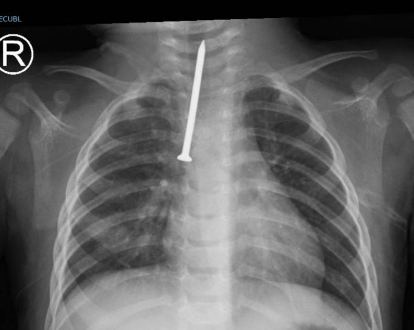

وفي التفاصيل، أجرى الفريق الطبي عملية تنظير صلب للقصبة الهوائية، نجح خلالها في استخراج مسمار بطول 5 سنتيمترات، كان الطفل قد استنشقه بشكل غير متوقع، مما تسبب في دخوله في مجرى الهواء الرئيسي وتسبب في حالة صحية حرجة.

وأوضح رئيس قسم جراحة الصدر ورئيس الفريق الجراحي، الدكتور محمد العمصي، أن الطفل كان يعاني من صعوبة حادة في التنفس، ما استدعى التدخل العاجل لإنقاذ حياته وتفادي مضاعفات خطيرة نتيجة وجود جسم غريب بهذا الحجم في القصبة الهوائية.

وأضاف أنه جرى نقل الطفل بشكل عاجل إلى غرفة العمليات، وإجراء المنظار اللازم للقصبة الهوائية ومجرى التنفس، ومن خلاله تم استخراج المسمار بنجاح.